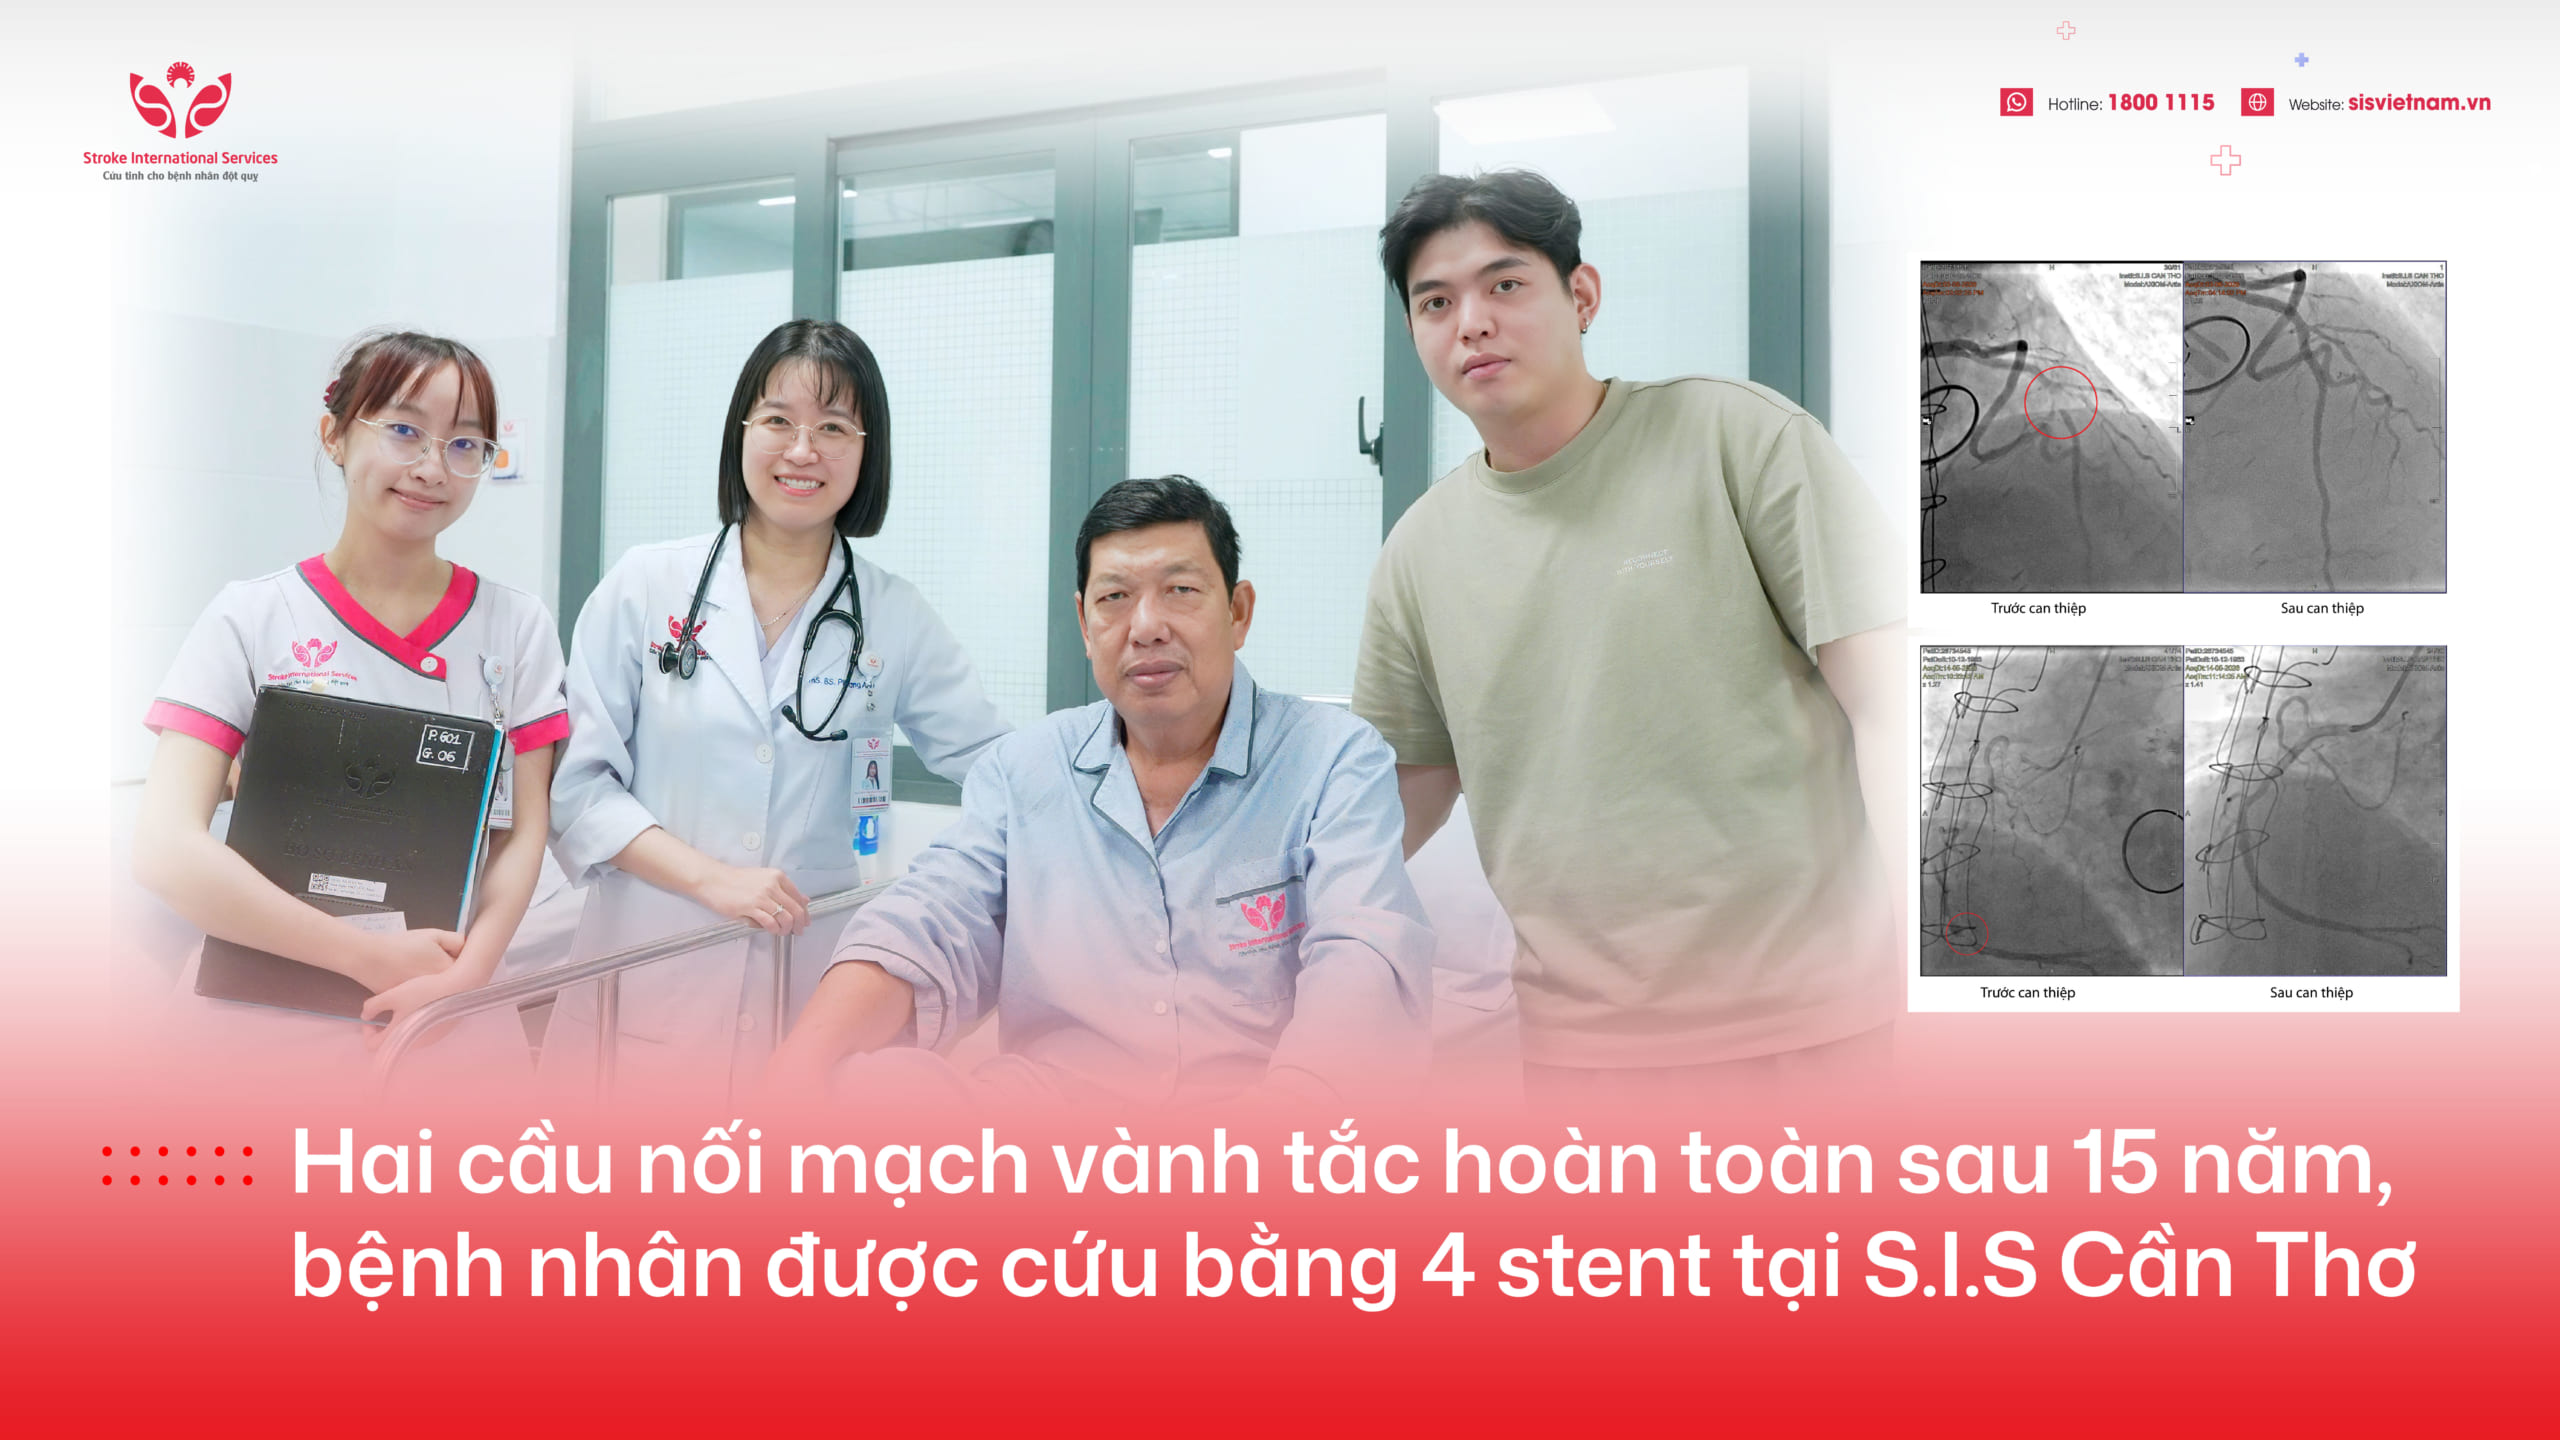

Bệnh viện Đa khoa Quốc tế S.I.S Cần Thơ vừa cứu sống ngoạn mục một người đàn ông bị nhồi máu cơ tim cấp, ngưng tim hai lần, hôn mê và tím tái toàn thân.

Tại Bệnh viện Đa khoa Quốc tế S.I.S Cần Thơ, ông L. được chẩn đoán nhồi máu cơ tim cấp ST chênh lên giờ thứ 3, ngưng tim với hồi sức thành công. Ngay lập tức, các bác sĩ chuyển ông đến Đơn vị can thiệp DSA để tiến hành chụp và nong mạch vành bị tắc nghẽn.

Kết quả chụp DSA cho thấy, nhánh động mạch vành phải của ông bị tắc hoàn toàn, trong khi nhánh liên thất trước của động mạch vành trái hẹp đến 90%.

Sau gần 50 phút, ekip can thiệp đã thành công đặt 1 stent vào nhánh động mạch vành phải, giúp tái thông dòng chảy máu cho tim. Sau can thiệp, bệnh nhân hồi phục kỳ diệu. Chỉ ba giờ sau, dù vẫn thở máy, ông L. đã tỉnh táo, nghe hiểu và không có dấu hiệu tổn thương thần kinh.

Sau hai tuần điều trị tích cực, ông L. đã được xuất viện, với sức khỏe bình phục tốt, trong niềm vui của gia đình và bác sĩ.